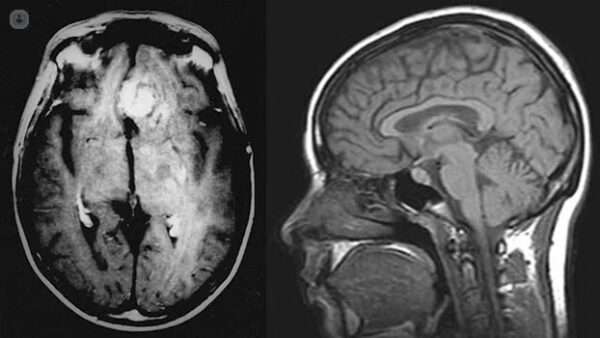

Hipertensión intracraneal idiopática

La hipertensión intracraneal idiopática, también conocida como pseudotumor cerebri, puede ser causada por una variedad de factores. Una de las causas más relevantes es la trombosis del seno venoso transverso,…